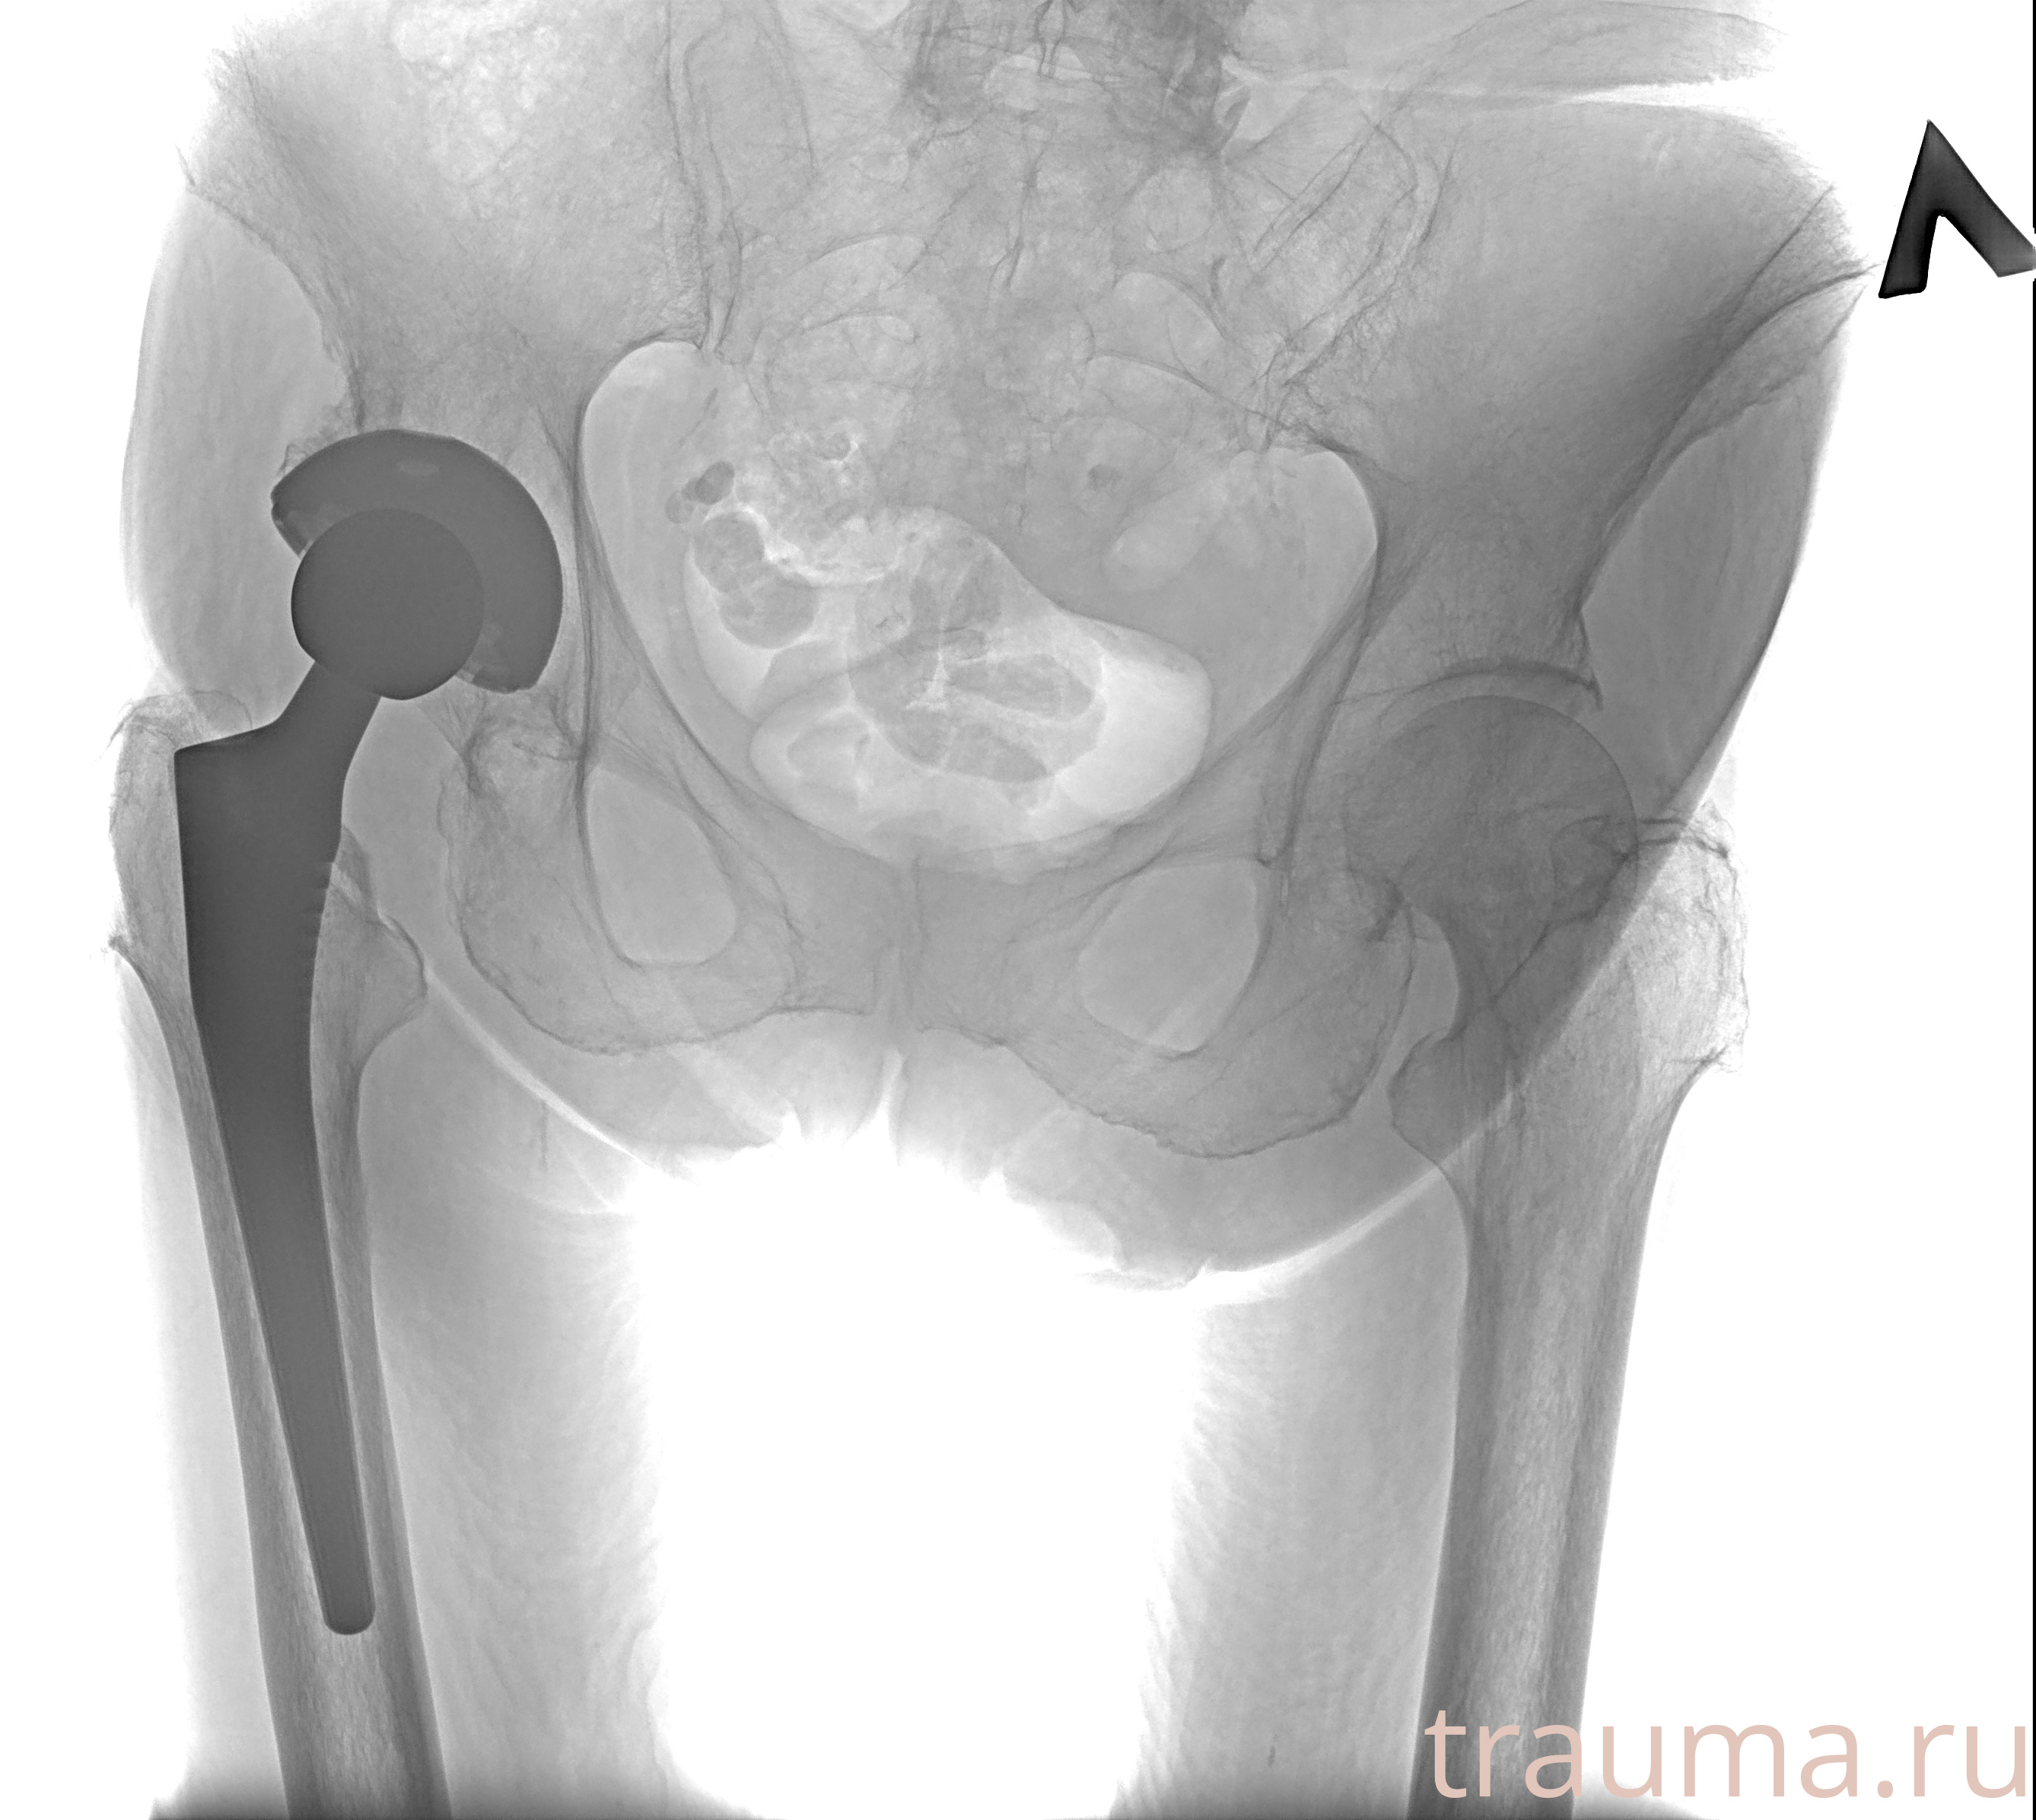

Рентген на дому: по вашему адресу приезжает врач-рентгенолог, травматолог-ортопед с мобильным рентгеновским аппаратом, проводит диагностику травмы или заболевания, делает необходимые рентгенограммы, дает рекомендации по дальнейшему лечению. Получить качественные снимки в домашних условиях возможно благодаря уникальной методике, разработанной МосРентген Центром для института  Склифосовского